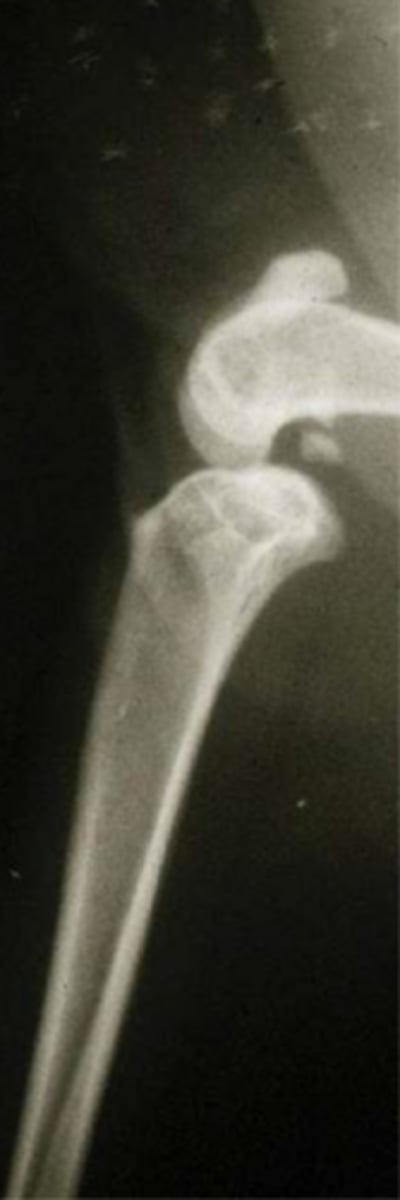

caudal cruciate lig. rupture

what is shown here...